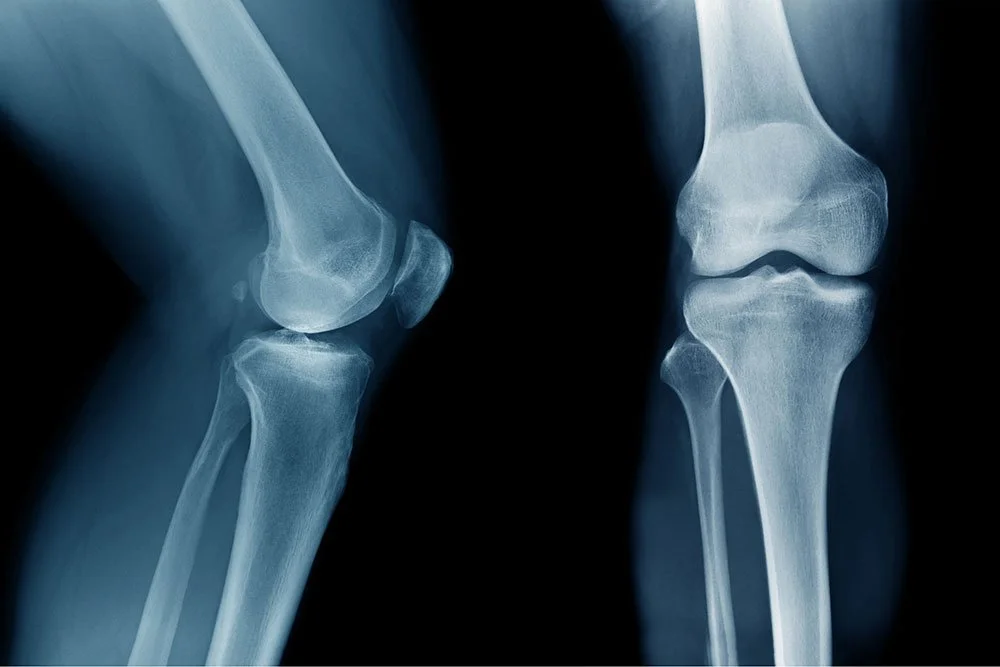

Does ACL Reconstruction Lead to Knee Replacement?

"We often see patients concerned about the long-term effects of ACL reconstruction," notes Dr. Cafferky. "One of the primary concerns is whether ACL reconstruction leads to knee replacement after ACL surgery." The ACL, or anterior cruciate ligament, is crucial for knee stability, and injuries to this ligament often necessitate surgical intervention.

Dr. Cafferky explains, "While ACL reconstruction can restore stability and function to the knee, it doesn't eliminate the risk of future issues. Patients frequently ask about the likelihood of knee replacement after ACL surgery, and it’s important to understand that various factors contribute to ACL reconstruction and knee replacement."

One significant factor is the development of osteoarthritis in the knee. "There is evidence suggesting a faster onset of arthritis after ACL surgery," says Dr. Cafferky. "This can be due to changes in knee mechanics and the initial injury's impact on the joint surfaces."